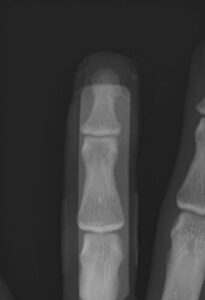

第16回整骨研究会「賜恩」研修会開催

さわやか千葉県民プラザ(指骨骨折)

第18回整骨研究会「賜恩」研修会開催